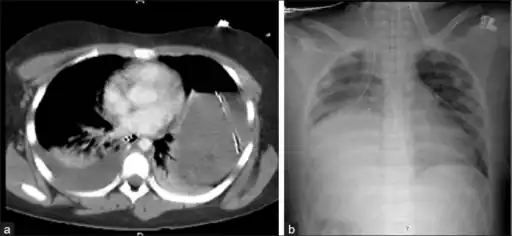

An X-ray showing a raised diaphragm on the right due to a rupture of the diaphragm on that side.[1]

Physical examinations are not accurate, as there is usually no specific physical sign that can be used to diagnose this condition.[6] Thoracoscopic and laparoscopic methods can be accurate.[15] Chest X-ray is known to be unreliable in diagnosing diaphragmatic rupture;[7] it has low sensitivity and specificity for the injury.[8] Often another injury such as pulmonary contusion masks the injury on the X-ray film.[9] Half the time, initial X-rays are normal; in most of those that are not, hemothorax or pneumothorax is present.[7] A nasogastric tube from the stomach may appear on the film in the chest cavity; this sign is pathognomonic for diaphragmatic rupture, but it is rare.[7] The X-ray is better able to detect the injury when taken from the back with the person upright, but this is not usually possible because the person is usually not stable enough; thus it is usually taken from the front with the person lying supine.[8] Positive pressure ventilation helps keep the abdominal organs from herniating into the chest cavity, but this also can prevent the injury from being discovered on an X-ray.[7]

A CT scan has an increased accuracy of diagnosis over X-ray,[10] but no specific findings on a CT scan exist to establish a diagnosis.[12] The free edge of a ruptured diaphragm may curl and become perpendicular to the chest wall, a sign known as a dangling diaphragm. A herniated organ may constrict at the location of a rupture, a sign known as the collar sign. If the liver herniates through a rupture on the right side, it may produce two signs known as the hump and band signs. The hump sign is a form of the collar sign on the right. The band sign is a bright line that intersects the liver. it is believed to result due to the ruptured diaphragm compressing.[16] Although CT scanning increases chances that diaphragmatic rupture will be diagnosed before surgery, the rate of diagnosis before surgery is still only 31–43.5%.[10] Another diagnostic method is laparotomy, but this misses diaphragmatic ruptures up to 15% of the time.[7] Often diaphragmatic injury is discovered during a laparotomy that was undertaken because of another abdominal injury.[7] Because laparotomies are more common in those with penetrating trauma than compared to those who experienced a blunt force injury, diaphragmatic rupture is found more often in these people.[17] Thoracoscopy is more reliable in detecting diaphragmatic tears than laparotomy and is especially useful when chronic diaphragmatic hernia is suspected.[7]